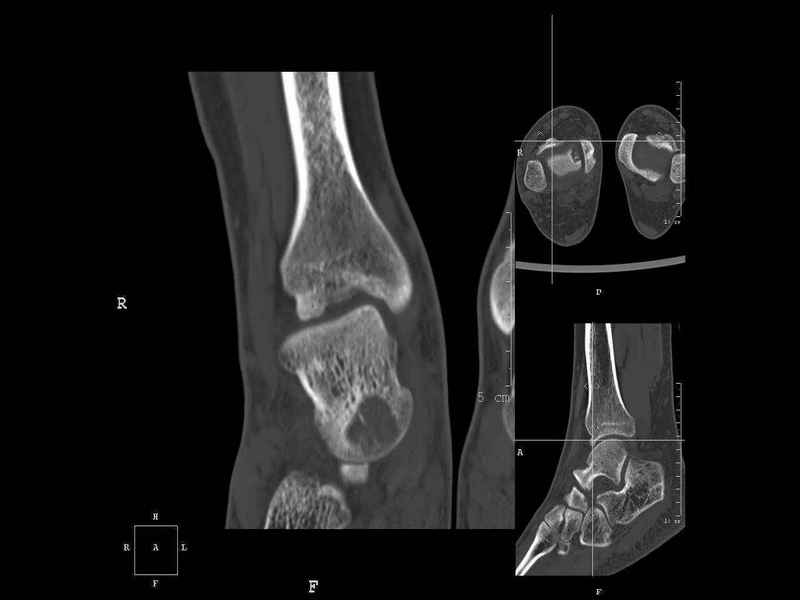

Рассекающий остеходрит + киста шейки тарана

Уважаемые коллеги, обратился за помощью пациент, мужчина, 25 лет. С жалобами на болевой синдром в области голеностопного сустава и среднем отделе стопы.

Травму отрицает. Со слов, болевой синдром в течении 1 года. Последние 1-1.5 мес периодически вынужден пользоваться костылями. После ограничения нагрузки боли уменьшаются. Соматически здоров. До появления болей активно занимался рукопашным боем.

На СКТ картина рассекающего остеохондрита блока таранной кости, киста шейки таранной кости с признаками импрессии суставной поверхности. А также - разрастания переднего края б\берцовой кости сопровождающиеся клиникой импиджмент синдрома.

Предполагаемый план лечения- удаление свободного фрагмента суставного хряща из трансмаллеолярного доступа с рассверливанием поверхности дефекта, кюретаж кисты шейки с заполнением полости биокомпозитом + дебридмент переднего отдела голеностопного сустава.

Прошу высказать своё мнение, за и против, предполагаемого плана лечения.

1. Есть ли необходимость в улучшении васкуляризации таранной кости (например подтаранный артродез).

2. Учитывая планируемое применение биокомпозитного цемента целесообразно ли заполнение им дефекта блока таранной кости с моделированием края суставной поверхности.